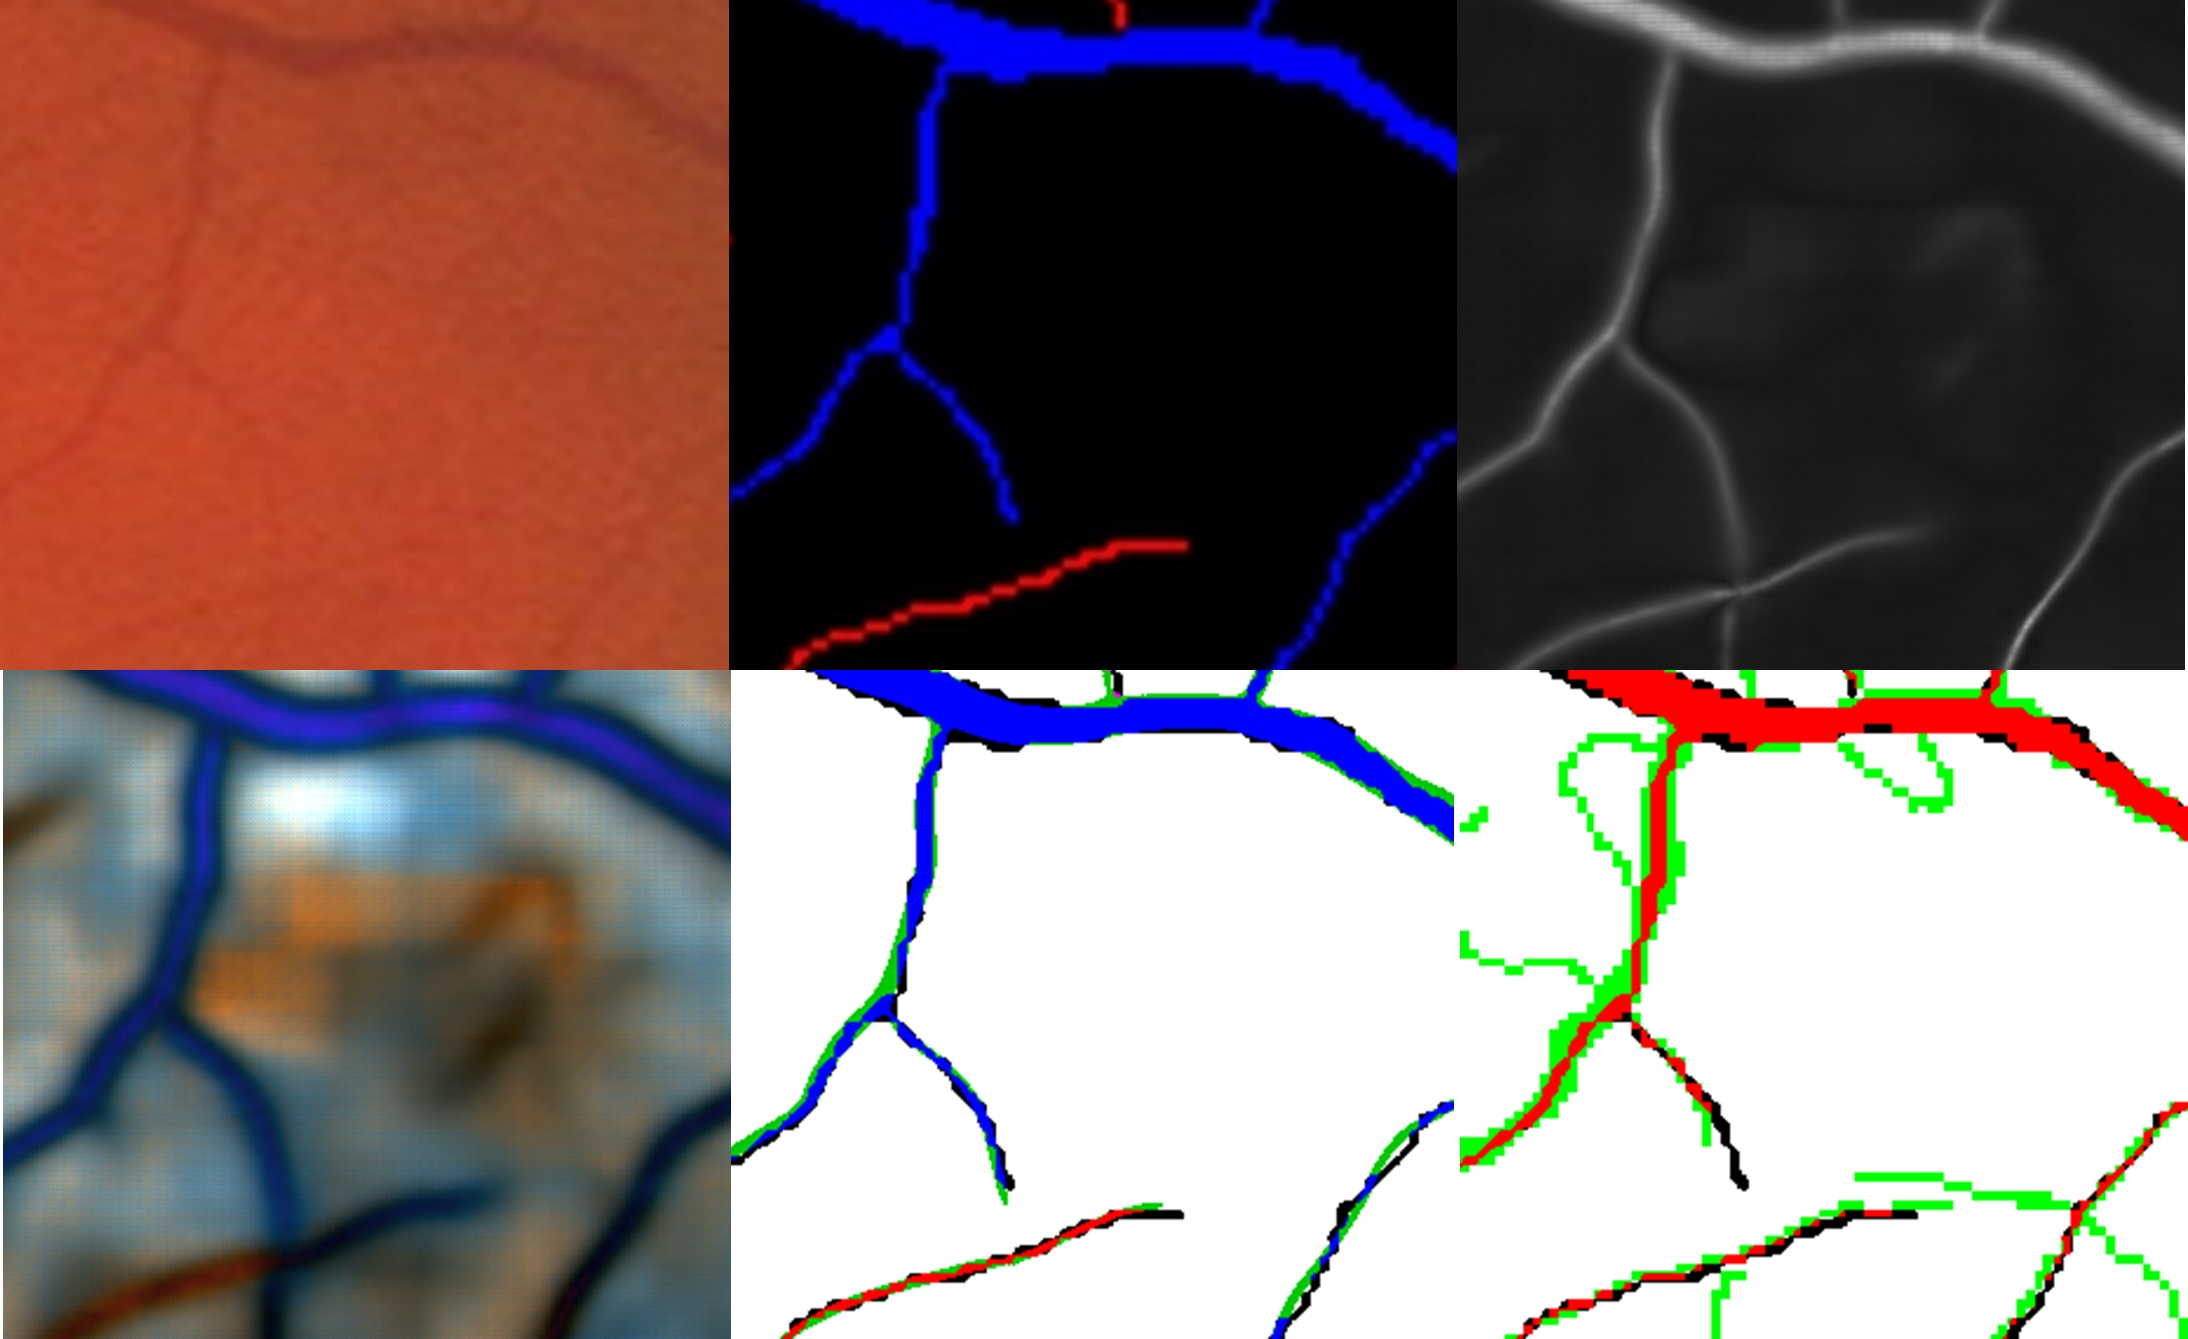

Analysis of the false negatives and false positives in the fundus images can help to better understanding the remaining errors. In Fig. 11 and Fig. 12, two examples of outputs are given. The false negatives are mainly small vessels that are not detected at all or are offset from their ground-truth locations. In Fig. 12, some hemorrhages are also detected as vessels. In the vessels wider than 4 pixels, the false positives are concentrated at the borders of those vessels. In the vessels narrower than 4 pixels, the false positives are mainly due to their being offset from their ground-truth locations. Misclassification of arteries as veins or vice-versa is mainly concentrated on vessels narrower than 4 pixels. There are also some arteries and veins interlaced or very close to each other, also causing misclassification.

These errors are very similar to what human observers (in this case, the second expert) would make compared to the gold standard (see Fig. 13, Fig. 14 and Fig. 15).